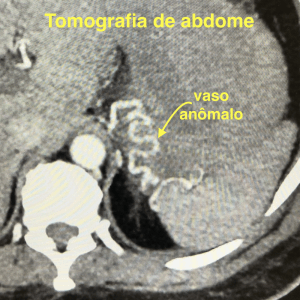

Existem diversas causas possíveis de sangramentos digestivos, como por exemplo, neoplasias, úlceras, varizes esôfago-gástricas, divertículos, aneurismas viscerais e angiodisplasias. Grande parte das hemorragias digestivas são auto-limitadas, ou seja, melhoram com medidas clínicas, entretanto, em algumas situações pode ser necessário um procedimento de embolização para controle do sangramento.

Um pequeno cateter é introduzido por meio desse furinho, de forma indolor, e então navega por dentro das artérias até chegar ao ponto onde esteja ocorrendo o sangramento.

Em seguida, o médico Radiologista Intervencionista provoca a oclusão dessas artérias (embolização), a fim de obstruir o seu fluxo sanguíneo e, consequentemente, o sangramento. Ao final do procedimento retiram-se os cateteres e é feito um curativo no local do furinho.